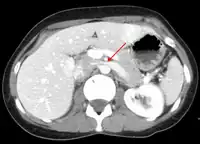

- Thrombosis in the left renal vein associated with dilation